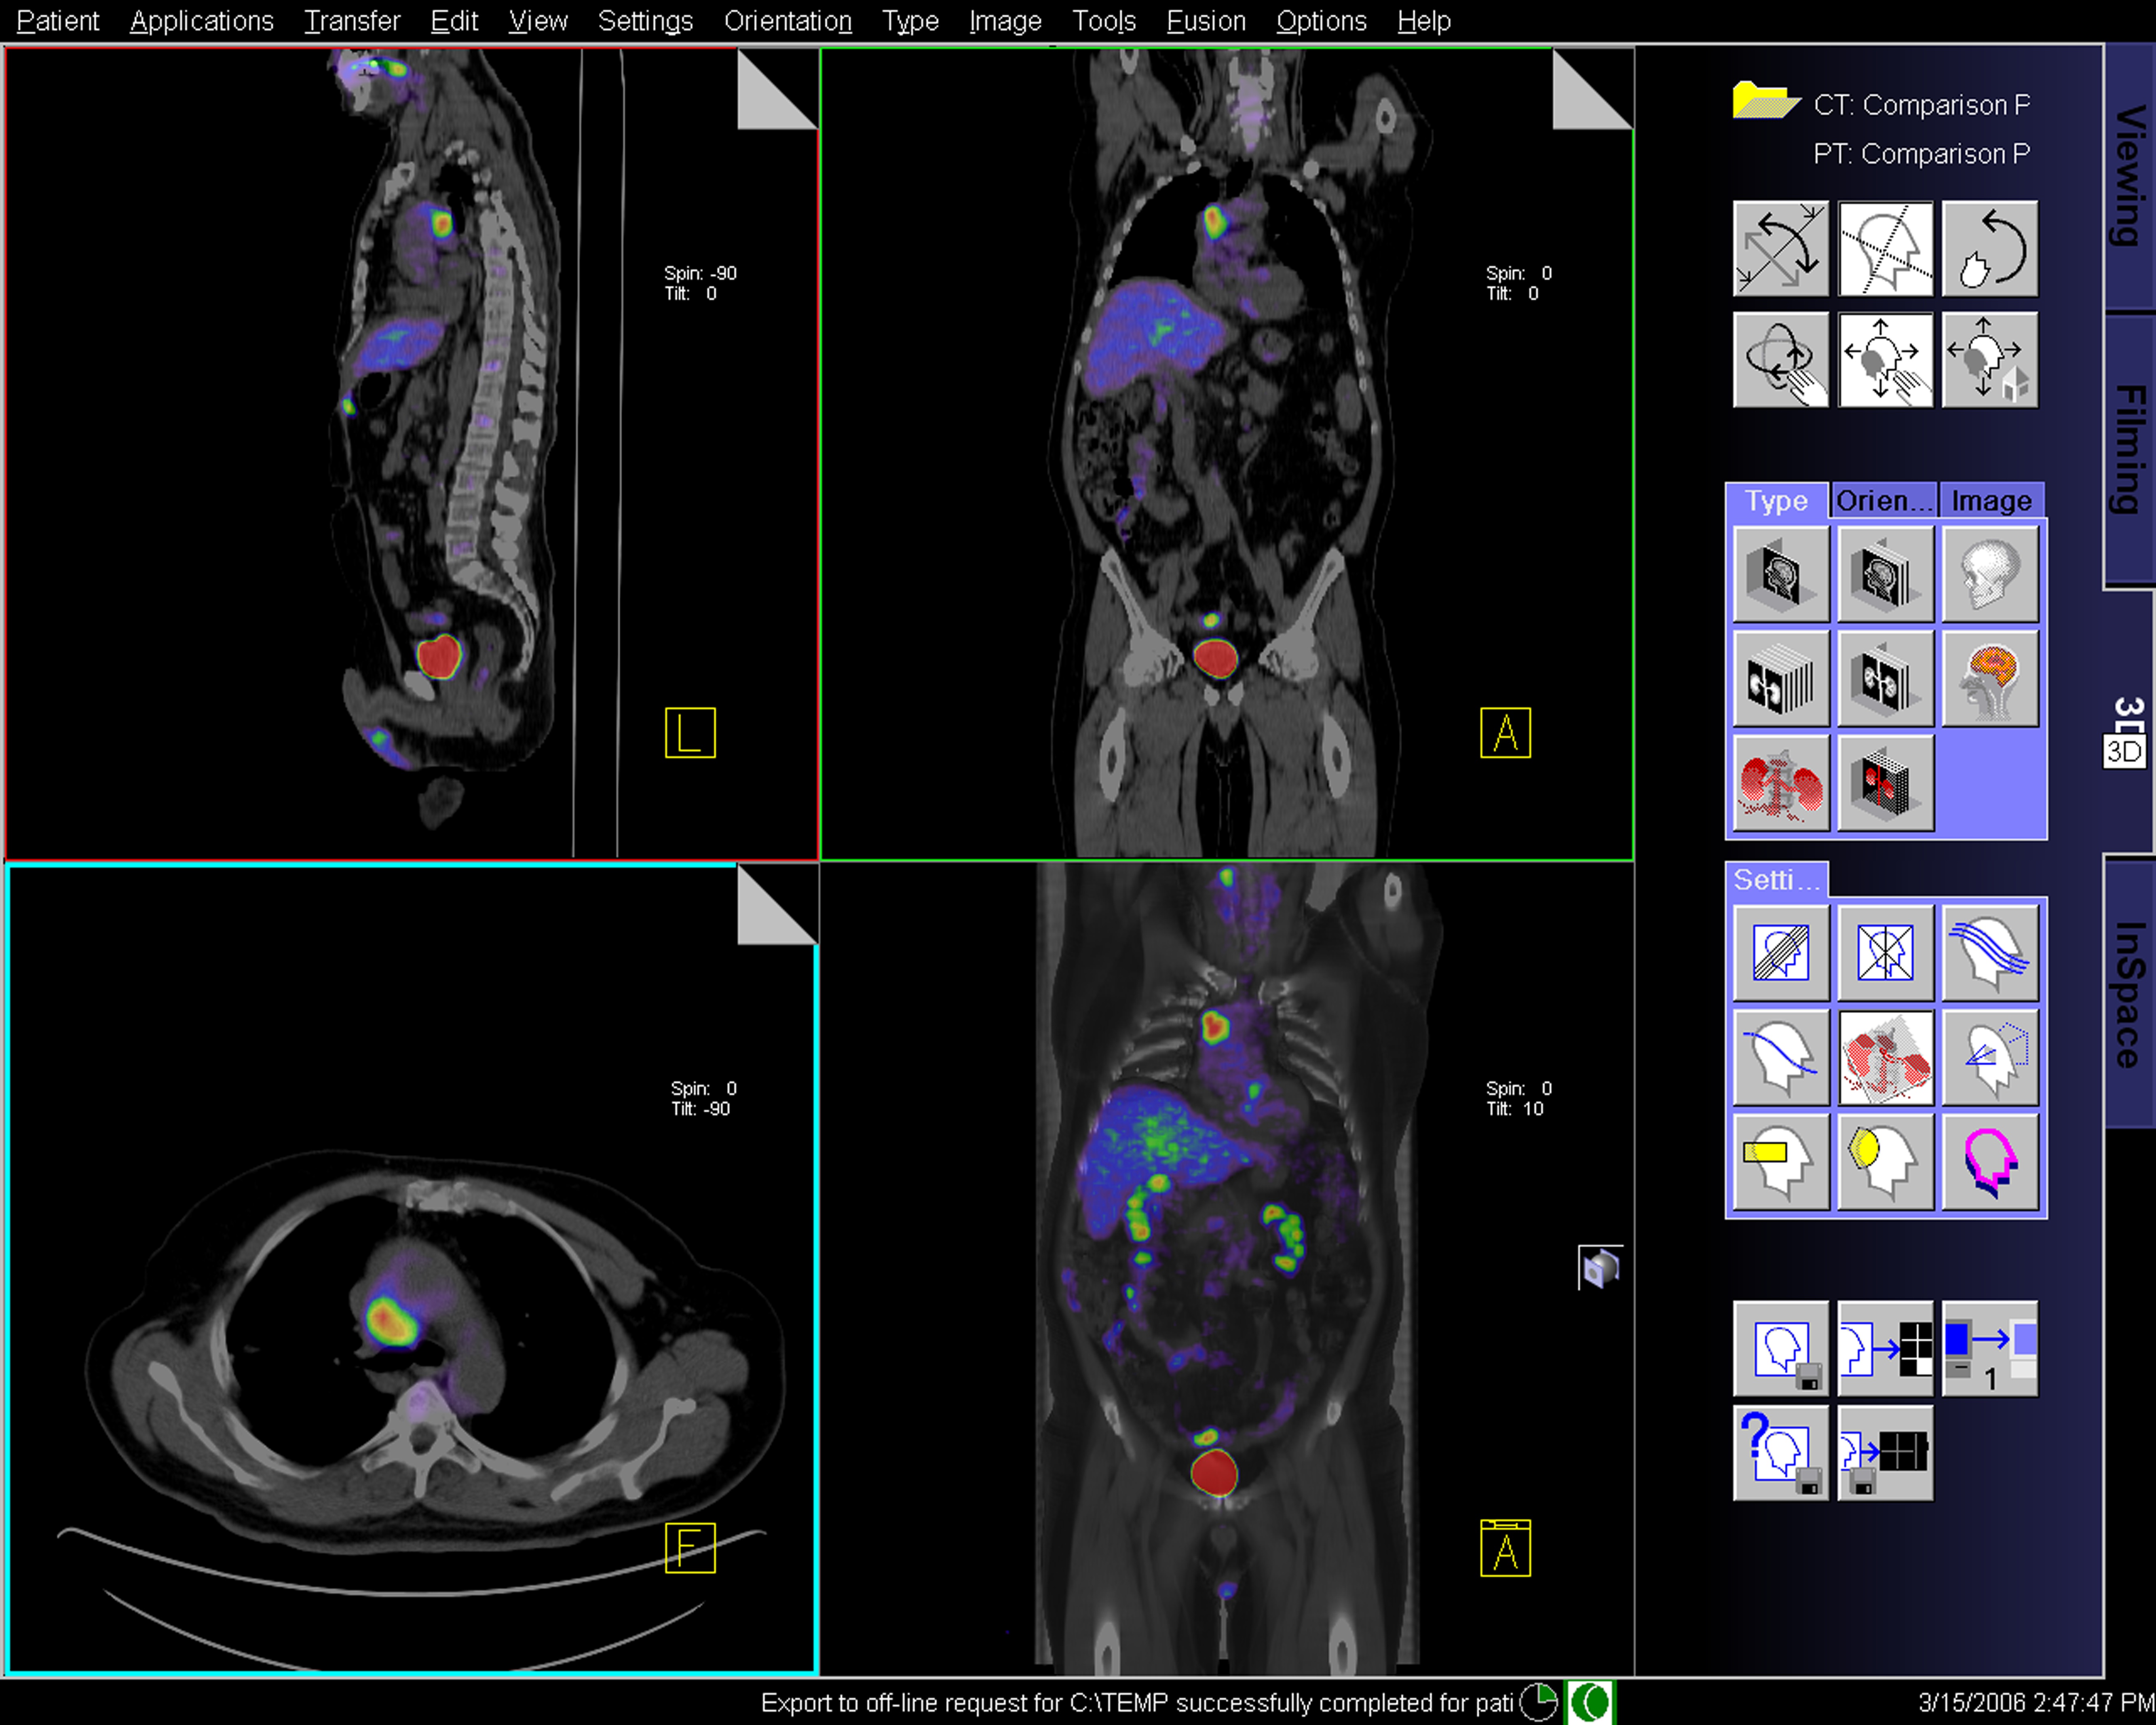

PET Imaging in Clinical Oncology | SpringerLink。Technology Focus – Diagnostic PET/CT Scan at Summit Cancer。What Does PET Imaging Bring to Neuro-Oncology in 2022? A Review。PETによるがん診断の専門書で、詳細な技術情報を提供。BLS 一次救命処置 AHAガイドライン2020準拠 プロバイダーマニュアル。。PET Scans Can Spare Lymphoma Patients Intensive Chemo。- タイトル: PET in Clinical Oncology- 著者: Helmut J. Wieler, R. Edward Coleman- ISBN: 978-3-7985-1219-1- 出版社: Springer- 言語: 英語- 内容: PETによるがんの診断と治療に関する詳細な情報を提供する専門書。ご覧いただきありがとうございます。医学生・研修医のための神経内科学